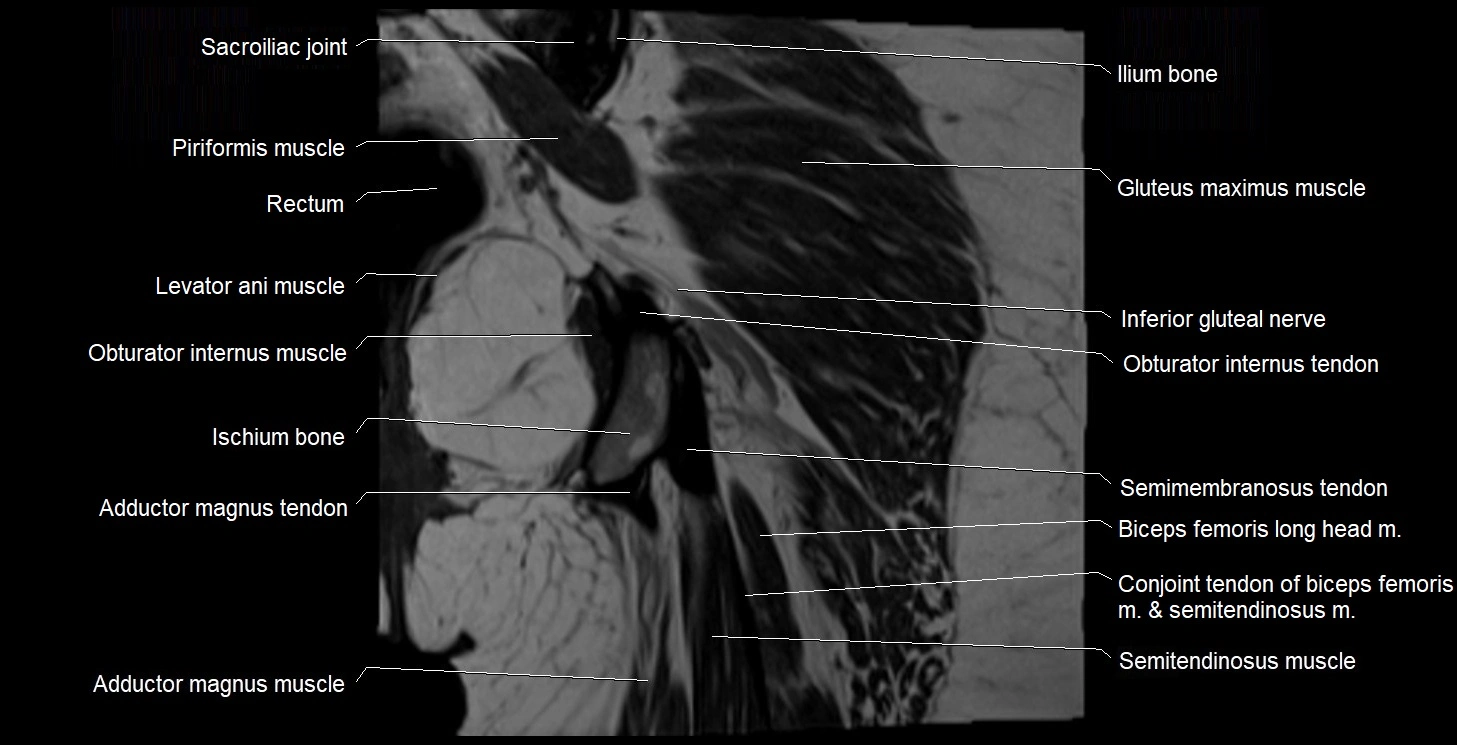

- Conjoint tendon of biceps femoris & semitendinosus

- Gluteus maximus muscle

- Iliococcygeus muscle

- Ischium bone

- Levator ani muscle

- Obturator internus muscle

- Obturator internus tendon

- Rectum

- Sacroiliac joint

- Semimembranosus tendon (proximal)